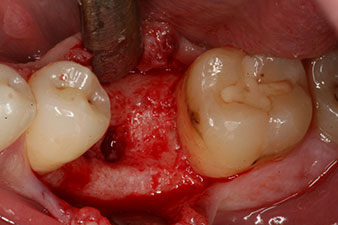

Cependant, six semaines après l’extraction on observe une ossification incomplète après la préparation du lambeau mucopériosté dans la région de l’ancienne alvéole mésiale.

L’implant a été posé comme prévu après élimination complète du tissu de granulation (blueSky, bredent).

Ces valeurs auraient pu indiquer une cicatrisation ouverte, voire une restauration immédiate. Étant donné le volume osseux crestal insuffisant au niveau de l’implant, une augmentation osseuse a été pratiquée localement à l’aide des fragments osseux recueillis lors de la préparation du lit implantaire, et des points de suture effectués pour éviter le contact de la salive.